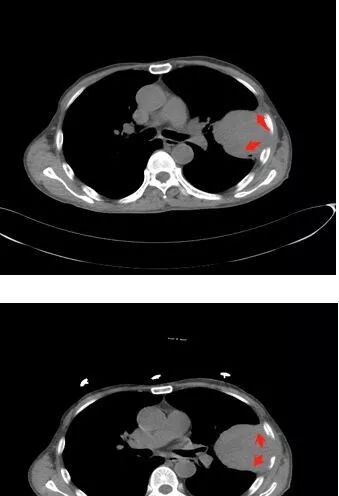

• 患者老年男性,因摔伤致腰部、双侧髓部疼痛2月余就诊

• 胸CT:左肺上叶实性占位,病灶与支气管无关,病灶对斜裂挤压,病灶周围光滑,未见分叶、毛刺;纵隔窗可见病灶内低密度区,病灶对胸壁侵袭,并可见肋骨破坏。

• 考虑恶性病变:肉瘤?肉瘤样癌?

患者中老年男性,外伤后入院。胸部CT:左肺上叶实性肿块,近心侧边界清楚,边缘光滑,胸壁侧突破壁层胸膜、肋间隙并侵犯肋骨及肋间肌,增强扫描轻度强化,可见近心侧多发片状坏死,未见明显淋巴结肿大。综合考虑SFT,鉴别肉瘤及结核。

胸部CT所见左肺上叶尖后段胸膜下较大山丘形肿块,边界清楚,宽基底与胸膜相贴,边缘与胸膜呈直角及锐角相交。邻近上叶尖后段支气管受压推挤,叶裂局部膨隆,病灶周围见少许磨玻璃密度影,边界不清。纵膈窗显示,肿块密度均匀,增强扫描呈不均匀轻度强化,邻近肋骨骨质破坏,病变沿肋间隙向外侵犯,局部胸膜增厚。纵膈内见多发小淋巴结,未见胸腔积液征象。综合考虑恶性占位,肉瘤样癌可能性大。腰椎及髋部考虑骨转移。